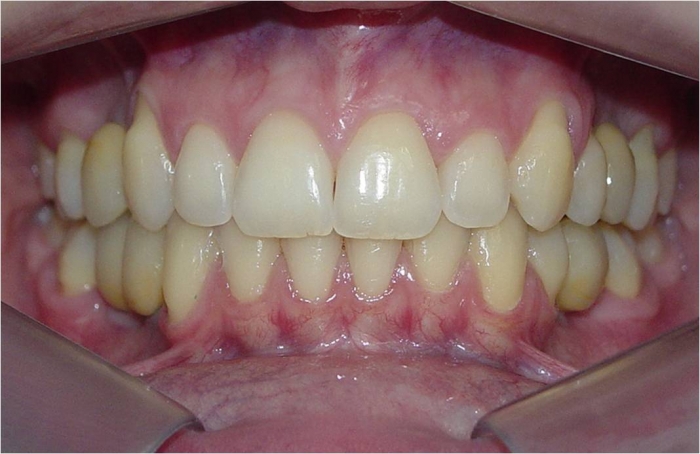

Sorriso inicial

Sorriso final, do caso terminado em Julho de 2014